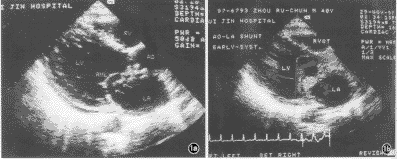

感染性心内膜炎导致主动脉-左房瘘一例

患者男,40岁,既往体健。1个月前开始发热,热型不规则,体温达39~40℃。曾在当地医院接受治疗,间断使用多种抗生素等药物。因病情未见减轻,并出现咳嗽、胸闷、心悸和夜间阵发性呼吸困难1周转来我院。入院时体温38℃,心率96次/分,血压120/75mm Hg(1 mm Hg=0.133 kPa),精神较萎靡,贫血貌,红细胞2.63×1012 /L,血沉120mm/1 h。听诊于胸骨左缘闻及连续性杂音,以收缩期为主,粗糙响亮;主动脉瓣区2~3级喷射性收缩期杂音 ......